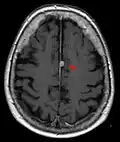

- T1-weighted (T1W) images: Cerebrospinal fluid is dark. T1-weighted images are useful for visualizing normal anatomy.

Brain regions on T1 MRI -

T1 (note CSF is dark) with contrast (arrow pointing to meningioma of the falx) -